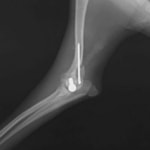

症例3:キルシュナーワイヤーのピンニングによる整復

ペルシャ猫 11ヶ月齢 雄

他院にて左大腿骨遠位の成長板骨折(salter-harrisⅠ型)が認められており、治療相談を目的として来院。当院にて、キルシュナーワイヤーを用いたピンニングにより骨折部位の整復を行いました。術後の経過は良好で、現在も経過観察中です。

術前レントゲン

術後レントゲン

機器

Arthrex社のターゲティングデバイスを用いてピンニングの位置を調整することで、確実な固定を行っています。当院ではこの手術器具以外にも、人の手術にも使用される様々な器具を導入し、手術精度を高め、また医療メーカーと新しい器具の開発、試作にも取り組んでおります。